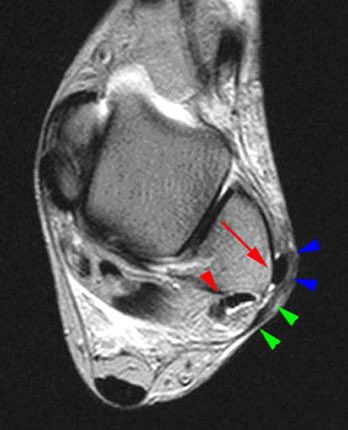

متلازمة هاجلاند : وهي إلتهاب في الجهة الخلفية من الكاحل ... وهو يلزم ثلاث متغيرات إشعاعية لتشخيصه من أهمها إلتهاب سفلي للوتر المعروف بوتر أكيليس

خلع في الوتر الشظوي وهو ما قد يتسبب في إلتهاب مزمن أو قطع